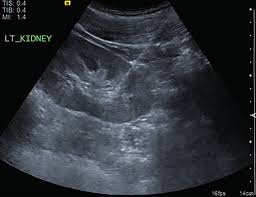

Monash PoCUS training support in Ultrasound Guidance for Renal Biopsies is offered to all Renal Unit registrars. PoCUS sessions are offered during registrar education time.